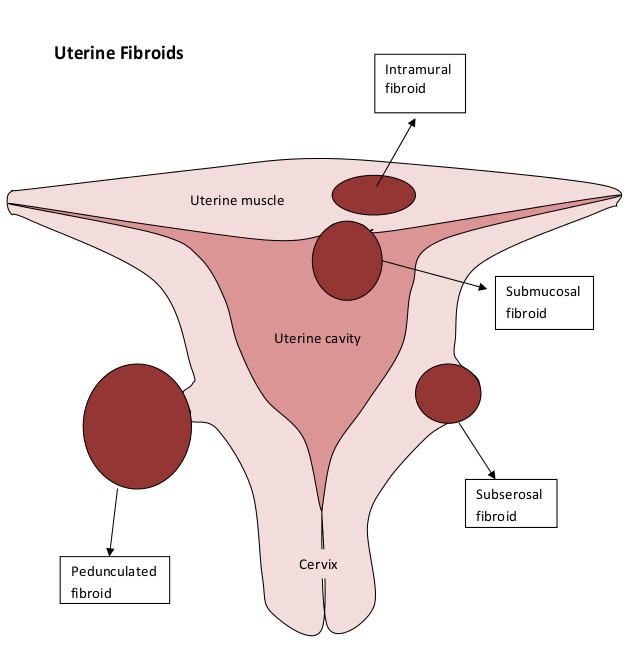

Types of Uterine Fibroids – Dr Pamela Tan | Uterine fibroids, Fibroids …

Types of Fibroid’s? | Fibroids, Hospital, Intramural

FIGO classification of uterine fibroids according to | Download …

Uterine fibroids. Fibroid types and uterine fibroids treatment | MED Expert